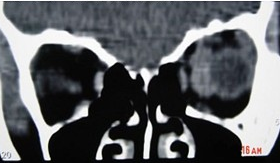

患者女性,3岁,右眼瞳孔区白色反光1年。CT检查:玻璃体有不规则的钙化斑块。最可能的诊断()

眼眶血管瘤的常见表现(),如图